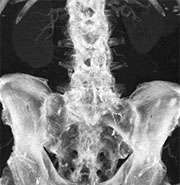

dual energy after bone removal

CT angiogram after automated bone removal displays aorta and iliac artery (red). Calcified plaque (yellow) limits evaluation of vessel stenosis.

dual energy post bone plaque removal

CT angiogram post automated bone and plaque removal clearly visualizes stenotic arterial segments.